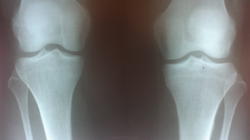

Уважаемый коллега! В посте коллеги Киреев Кондрат спрашивалось: " Очень много гипер и гиподиагностики. Довольно очевидный снимок, но все же. Есть ли тут артроз или нет?"

Суставная щель не изменена, всё остальное к артрозу отношения не имеет.

Нормальные коленки, я бы не ставила артроз

Если справа на снимке - левый сустав, то артроз 1 ст. в нём, то есть там!)

Сужение щели вижу один? В медиальном отделе? Или укладкой сужение мы объясним?)

Давайте будем адекватны, щели с 2 сторон не одинаковые, слева явно уже.При такой картинке без боковых делать заключение не стала бы.